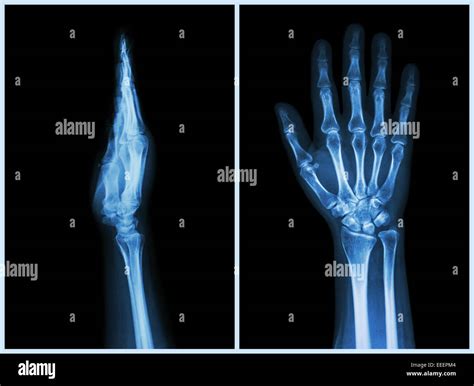

A Hand X Ray is a type of radiography that uses electromagnetic radiation to produce images of the internal structures of the hand. This process involves passing X-rays through the hand and capturing the resulting image on a detector. The varying densities of different tissues—such as bone, muscle, and fat—absorb the X-rays differently, creating a contrast that allows for detailed visualization.

• Fractures and Dislocations: X-rays are the primary method for diagnosing broken bones and dislocated joints in the hand.

• hand x ray positioning

• lateral hand x ray

• hand x ray views